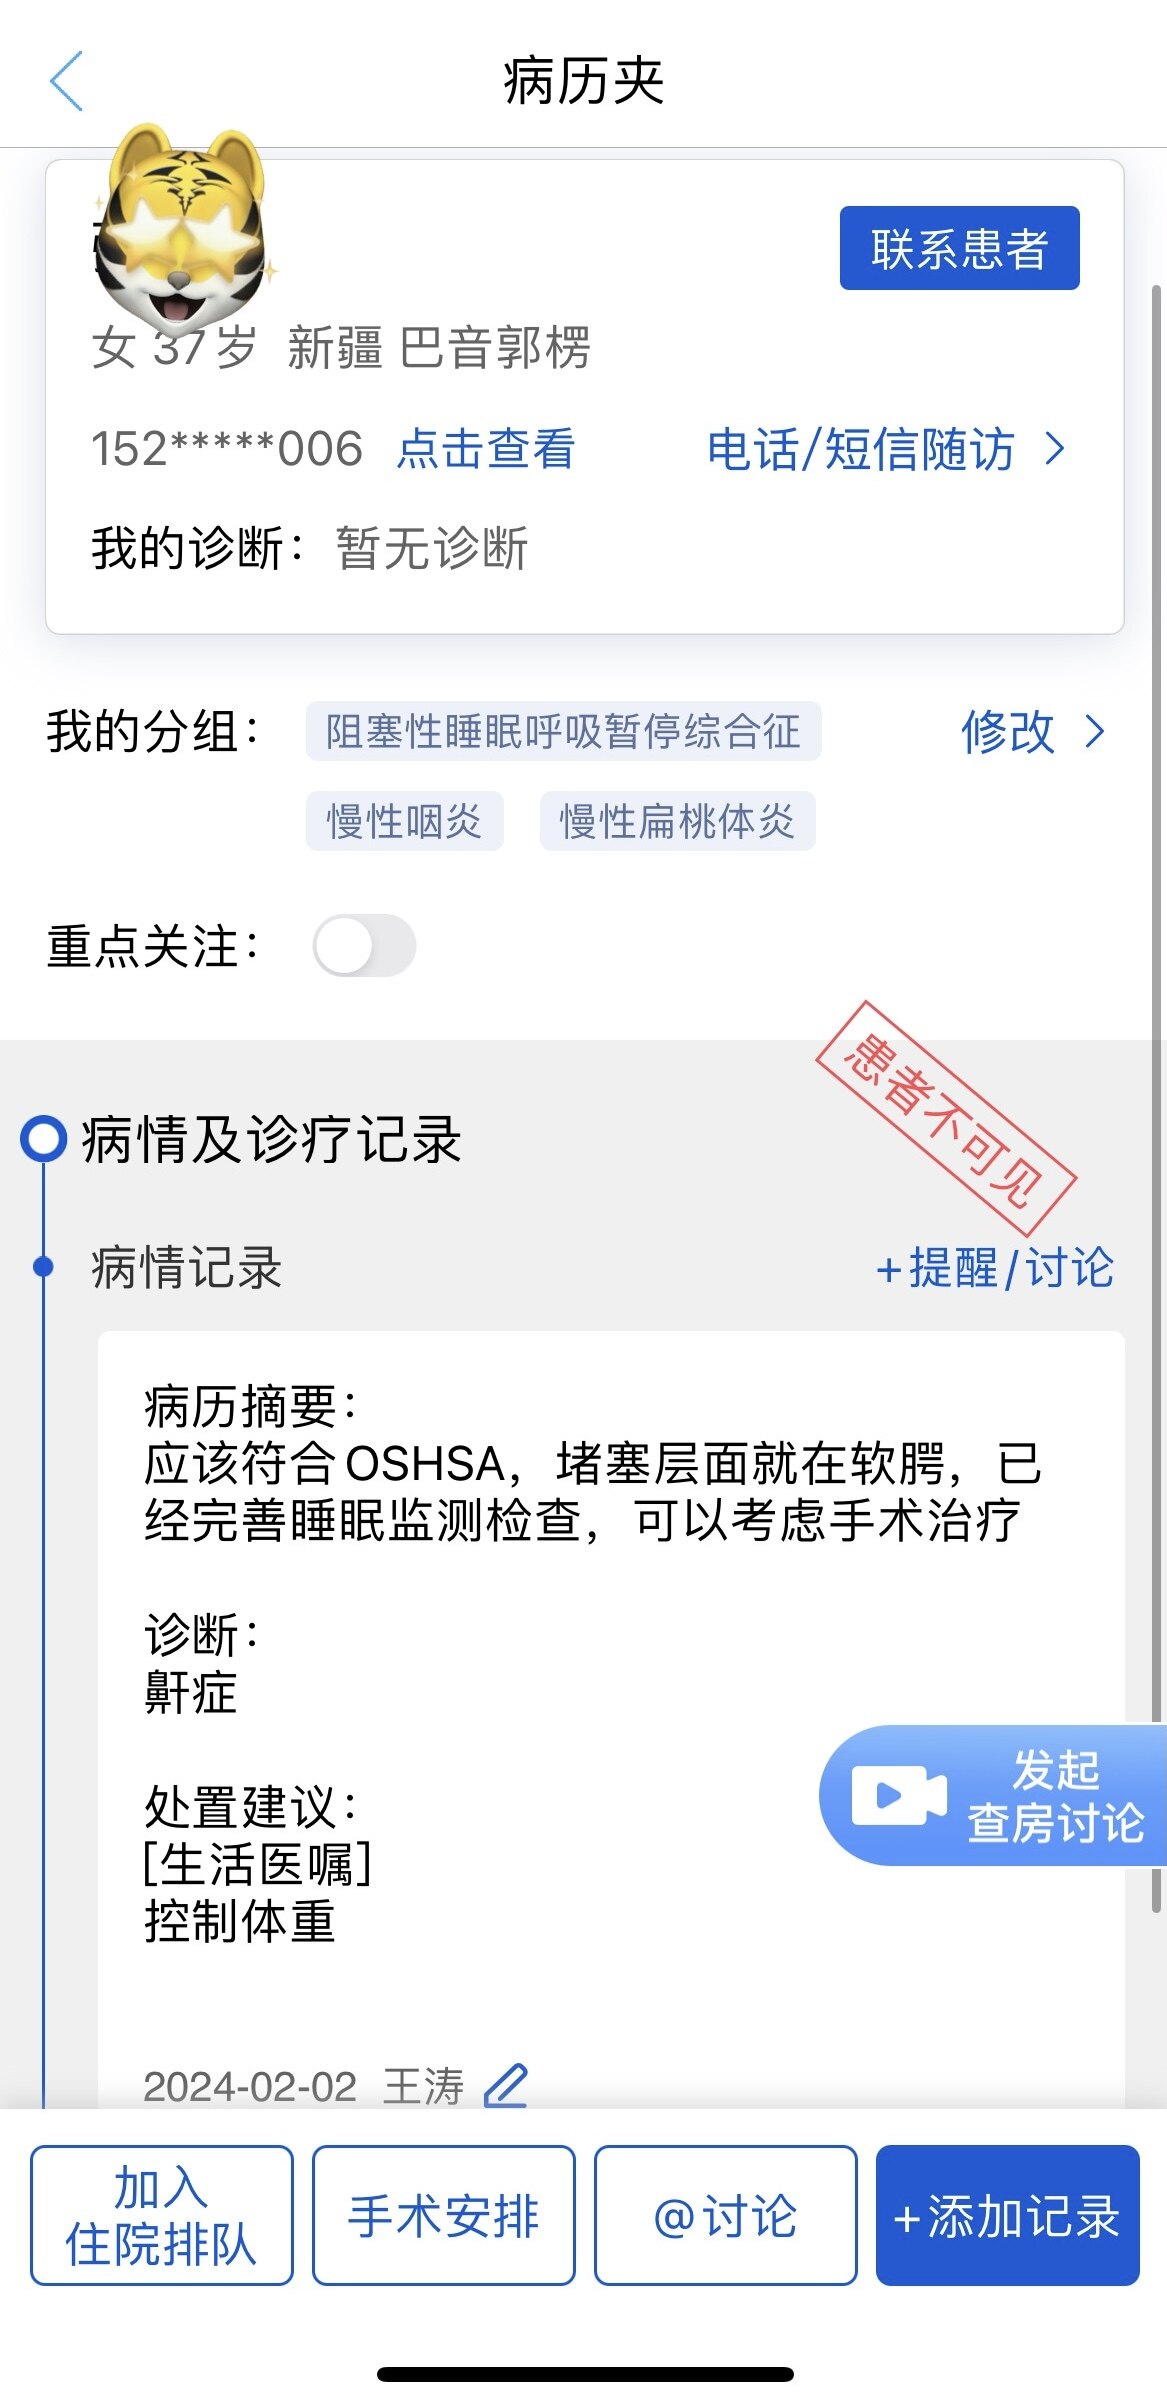

慕名而来的新疆“鼾症母女”在同一天顺利完成手术,真正告别打鼾和憋醒问题!

之前同一天做过“鼾症兄弟”、“鼾症兄妹”和“鼾症父女”,这是第一次给“鼾症母女”同一天手术。这对母女来自新疆巴音郭楞,重度鼾症父亲37岁,因为扁桃体肥大,自小打鼾,4年前产后打鼾加重,伴夜间憋醒,严重影响睡眠,当地医生建议患者戴呼吸机,但是她无法耐受呼吸机。电话咨询后,下定决心来广州找我手术。同时她也把4岁女儿打鼾和张口呼吸的情况也详细告诉我,鼾症女儿因为扁桃体3度肥大,腺样体堵塞后鼻孔2/3,造成张口呼吸,对于这样的孩子,一定需要早点手术干预,不然会影响面部发育和生长发育,甚至智力发育。所以我就让她们母女一起来广州找我手术。手术时发现母女俩的扁桃体肥大,因为女孩子4岁,我常规保留双下极扁桃体的1/5和腺样体的1/5。希望母女手术后身体早日恢复正常!有一个安稳的睡眠质量,健健康康的生活!